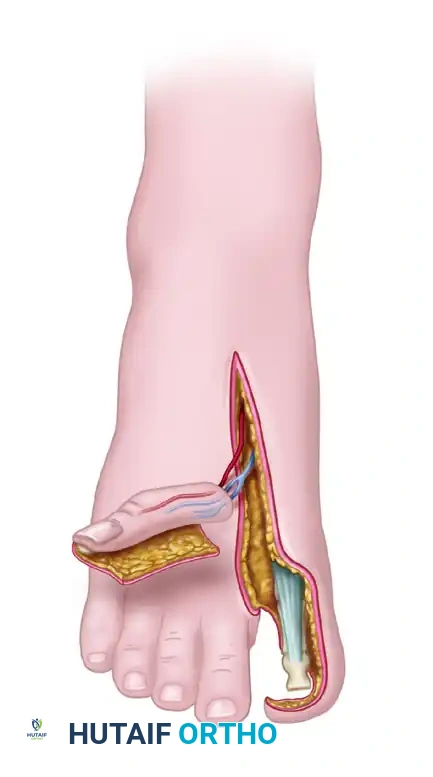

Flap Design and Incision

The skin flap is carefully outlined to deglove the entire great toe, with the critical exception of a thin longitudinal strip of skin extending to the lateral corner of the toenail.

The width of this preserved medial strip (usually about 1 cm) is determined by the exact amount of skin required to circumferentially cover the reconstructed thumb. This preserved strip ensures adequate venous and lymphatic drainage for the remaining toe structure.

Bone and Nail Harvest

- Separate the toe flap beneath the nail by gentle, sharp subperiosteal elevation.

Pitfall: Avoid any injury to the germinative layer of the nail matrix. Damage here will result in a deformed or absent nail on the reconstructed thumb.

- Using a fine osteotome or bone cutter, remove approximately 1 cm of the distal tuft of the distal phalanx, keeping it attached to the flap beneath the nail bed. This bone segment provides rigid support for the nail complex.

Flap Isolation

At this stage, the flap should be completely free from the toe, tethered only by its neurovascular pedicle (the dorsal digital branches of the FDMA and the saphenous venous tributaries).

Release the tourniquet. Confirm that the flap is adequately perfused by its arteriovenous pedicle.

* Note: It may take 30 to 60 minutes for the flap to turn completely pink due to vasospasm. Bathing the vessels in warm saline and topical lidocaine or papaverine is highly recommended to relieve spasm.

Once perfusion is confirmed and the recipient hand is fully prepared, apply microvascular clips to the vessels. Ligate or apply small hemoclips to the proximal vessels before sectioning them to harvest the flap.

DONOR SITE CLOSURE

While the microvascular anastomoses are being performed, Team A closes the great toe donor defect.

1. Ensure the paratenon over the extensor hallucis longus is preserved, as this provides the vascular bed for the skin graft.

2. Because 1 cm of the distal phalanx was removed, the preserved medial skin flap can be rotated over the tip of the toe to provide durable coverage over the bone end.

3. Apply a split-thickness skin graft to the remaining exposed plantar, dorsal, and lateral surfaces of the great toe.

4. Stent the graft with a tie-over bolster dressing to prevent shearing. Cross-toe flaps are rarely required if the skin graft is managed meticulously.